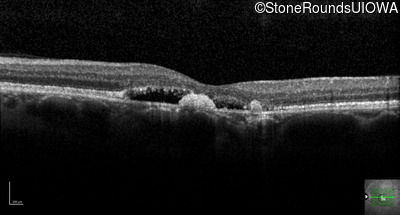

Optical Coherence Tomography - Right - 20/25 -2

Exemplar / OCT Stack